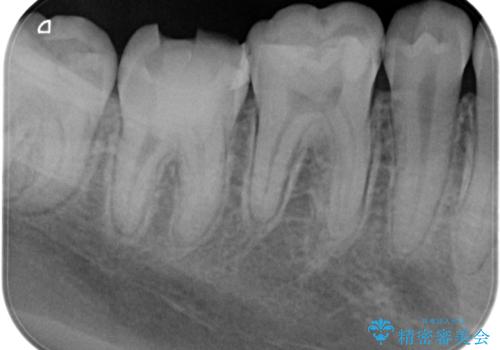

湾曲根管。精密根管治療

担当医 河口智英